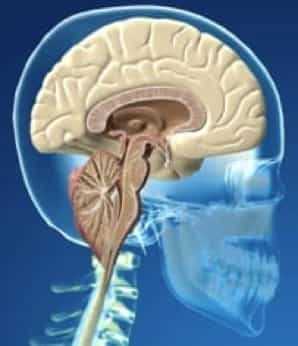

Мальформация Арнольда — Киари (МАК) — это патология развития ромбовидного мозга: продолговатого и заднего мозга, в последний входит Варолиев мост и мозжечок. При МАК задняя черепная ямка не соответствует мозговым структурам, расположенным в этой области: мозжечок и продолговатый мозг из‑за небольших размеров опускаются ниже большого затылочного отверстия, что приводит к их ущемлению и нарушению ликвородинамики. МАК относят к группе кранио-вертебральных (черепно-позвоночных) мальформаций.

В области соединения черепа с позвоночным столбом находится большое затылочное отверстие, на уровне которого ствол головного мозга переходит в спинной мозг. Выше этого отверстия локализуется задняя черепная ямка. В ней расположен мост, продолговатый мозг и мозжечок. Аномалия Киари связана с выходом части анатомических структур задней черепной ямки в просвет большого затылочного отверстия. При этом происходит сдавление находящихся в этой области структур продолговатого и спинного мозга, а также нарушение оттока цереброспинальной жидкости из головного мозга, приводящее к гидроцефалии. Вместе с платибазией, ассимиляцией атланта и др. аномалия Киари относится к врожденным порокам развития краниовертебрального перехода.

Рисунок 1.- На схеме показано опущение миндалин мозжечка и увеличение надмозжечкового пространства из-за смещения всего мозжечка к затылочному отверстию. Синдром Арнольда Киари I.